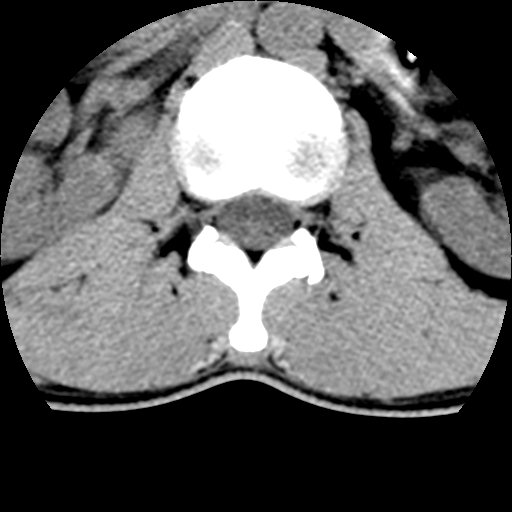

标题: CT10387:男,31岁,胸腰段CT [打印本页]

标题: CT10387:男,31岁,胸腰段CT

男,31岁,从6米高处坠落伤两天,腰背部疼痛,临床要求ct扫描胸10-腰1。请大家帮忙看看骨质有问题吗?

t12、l1锥体前缘轻度楔形变,平扫示椎体前缘骨小梁欠规整,第9幅图示椎体前缘骨质不连续,结合外伤史考虑椎体轻度压缩骨折。

楼主扫描层厚可能较大,每个椎体只有三个层面.

从所示层面分析,无明确骨折征象,象类似病人我个人会建议mri除外骨挫伤.

从上查骨窗第九片椎体前缘皮质显示断裂.压缩骨折?